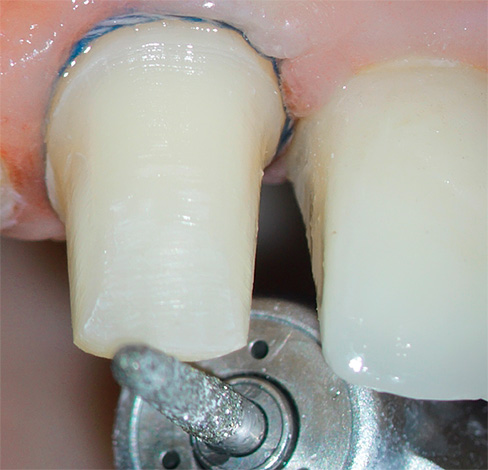

Uma das causas mais comuns de inflamação pulpar em um dente é o superaquecimento durante o "giro" do esmalte dentário. Alguns dentistas ainda trabalham sem o resfriamento da água na ponta da broca, o que ocasionalmente leva a uma queima do “nervo” durante o processamento de tecidos duros sob a coroa e subsequente necrose pulpar.

A coroa de metal-cerâmica requer um processamento significativo de esmalte de todas as 5 superfícies do dente. Dele, de fato, resta um coto, portanto, o médico deve cumprir estritamente todas as condições de trabalho: do conhecimento das zonas de segurança para impedir a proximidade de uma broca rotativa à câmara pulpar, ao uso de dicas modernas adaptadas ao arrefecimento por água e ar da área tratada por todos os lados. Se pelo menos uma condição for violada, o dente superaquece e subsequentemente começa a doer.Freqüentemente, nesses casos, o dente dói sob a coroa devido ao calor, e a dor não passa muito tempo depois de eliminar a fonte de irritação, muitas vezes se intensifica à noite.